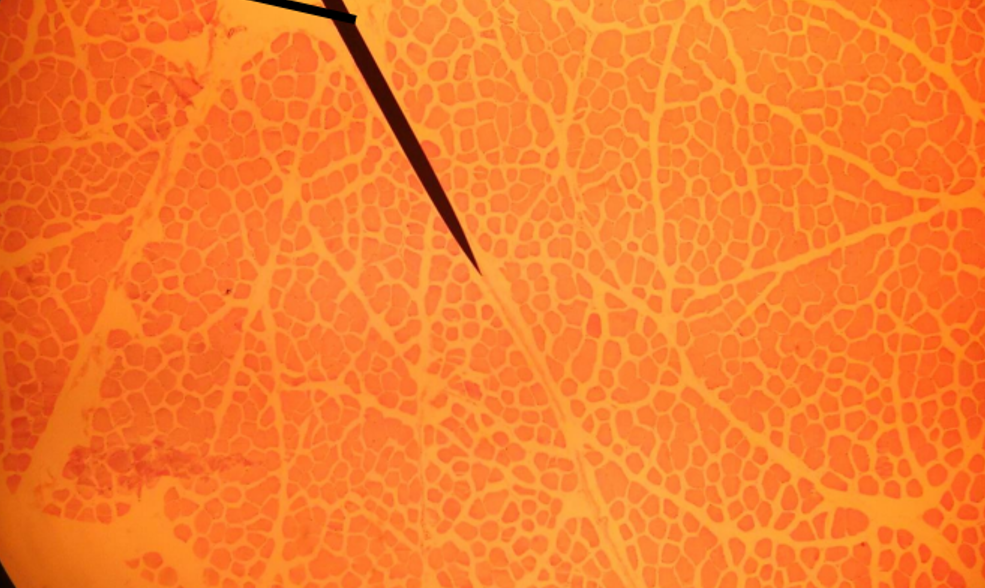

What is the pointer on?

perimysium

This is a cross section of what?

Skeletal muscle